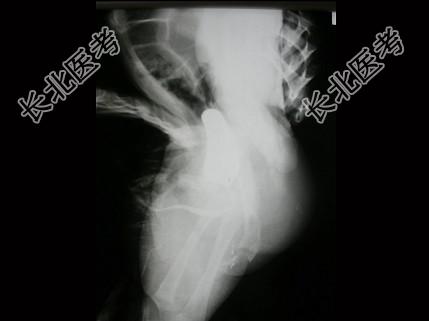

- 单项选择题男,4个月, 阴茎、排尿异常4个月,行尿道造影如图所示, 最可能的诊断是 ( )

A、正常尿道

B、尿道瓣膜形成

C、尿道下裂畸形

D、尿道憩室

E、尿道重复畸形